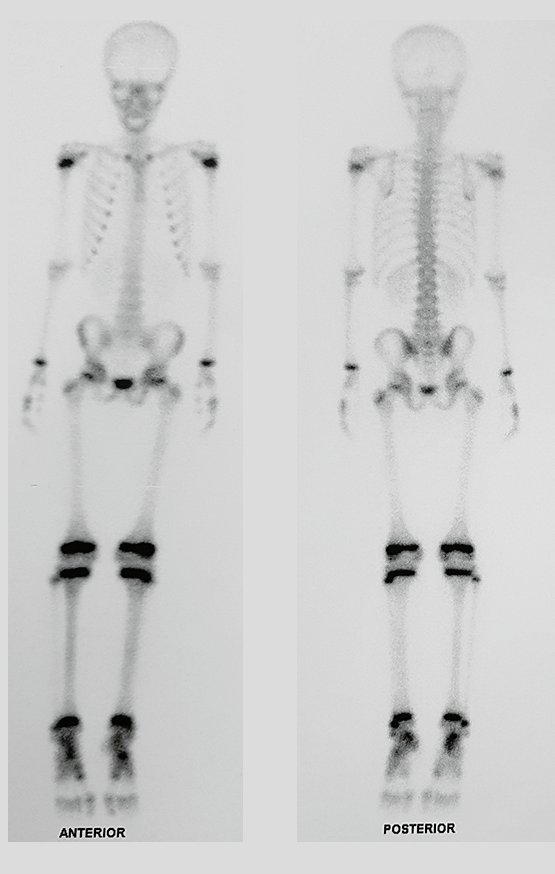

Simple Tibial Bone Cyst. An eight-year-old male patient suffered a fall with an abrasion on his right knee. He underwent an x-ray in the emergency room which revealed a bone rarefaction lesion in the proximal metaphysis of the right tibia, figures below.